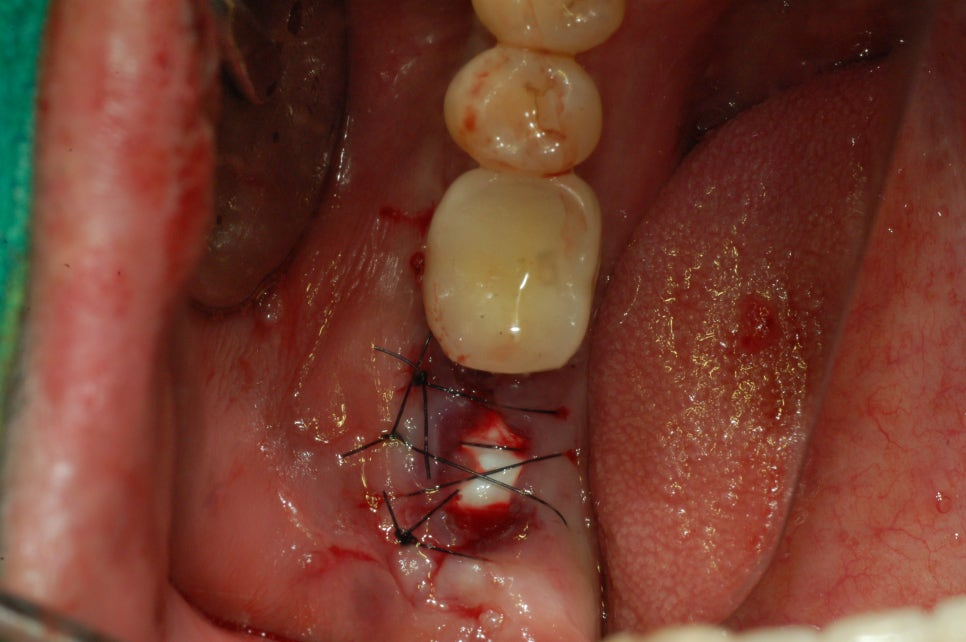

뼈이식 해야 할 자리를 확인 후 뼈이식을 하게 됩니다. 뼈이식을 한 후 그대로 나두게 되면 뼈가 제대로 안착이 될 수 없기 떄문에 뼈이식 한 곳 위에 멤브레인이라는 것을 얹혀놓고 실밥을 꿰매게 되는 과정을 거치고 있습니다.

상황에 따라 다르지만 필요에 따라 멤브레인을 사용하는 것이 뼈가 무너저 내리지 않고 뼈 이식재를 한번 더 감싸는 과정을 거친다~ 라고 보시면 좋을 것 같습니다. 꼼꼼히 실밥을 하여 쌓아 올린 탑이 무너지지 않도록 마무리 하는 것이 중요한 포인트 이기도 합니다^^